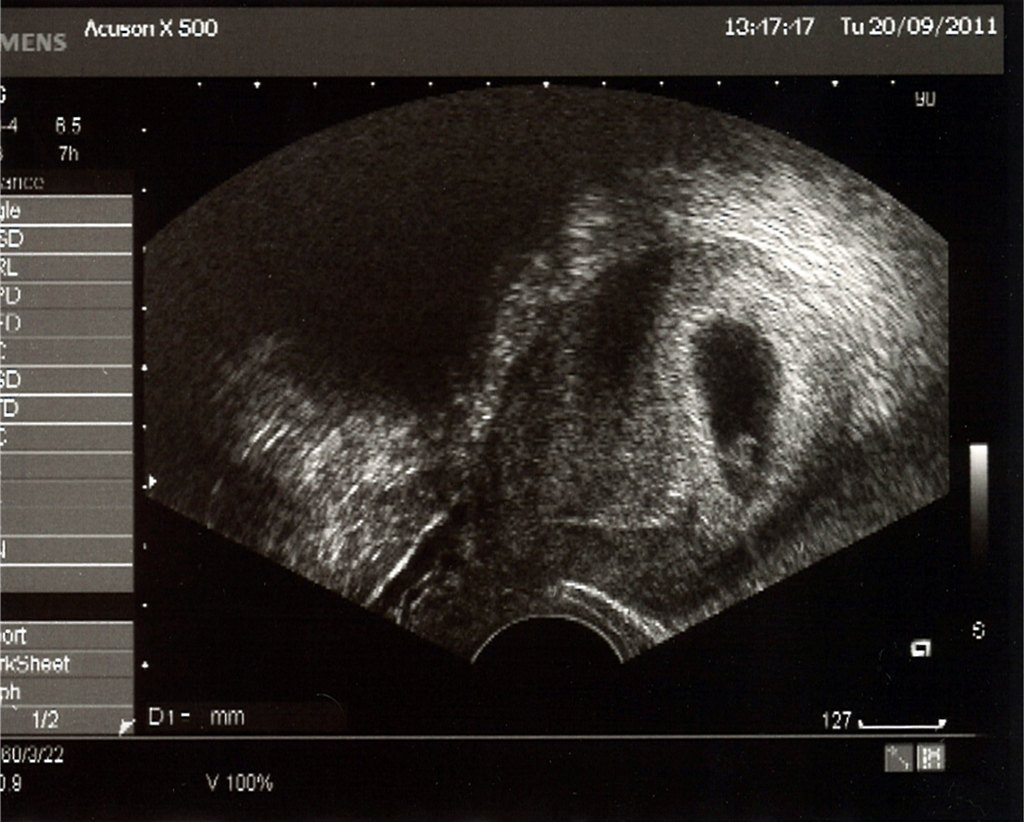

Vi kommer til scanning igår og ser den dejligste lille klump med blinkende hjerte Jeg begyndte at tude (øhh syntes jeg rimelig tit at jeg gør lige i tiden )

Vi fik dette skønne billede med hjem, dog ligner det ikke en baby endnu, men det er vores skønne bevis på at baby er der